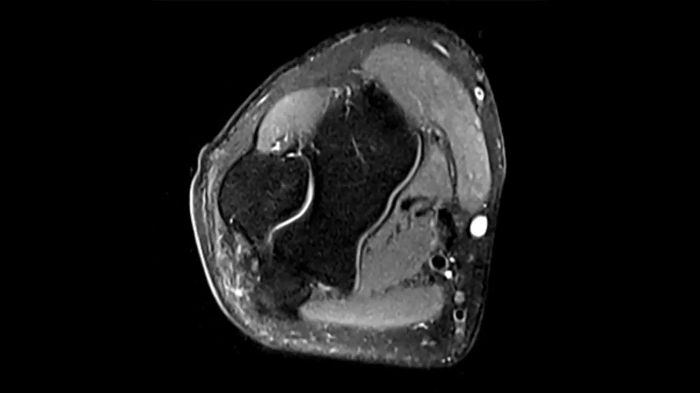

Knee

PD TSE Fat Sat with Deep Resolve and Simultaneous Multi-Slice

For clear imaging of the knee, outstanding fat suppression and performance are possible. Integrating the influence of Deep Resolve with the established Simultaneous Multi-Slice technique.

SMS 2 | Deep Resolve Gain & Sharp

0.4 x 0.4 x 3.0 mm2

TA 2:56 minutes

MAC-ID: 7aaaa0198. Image Credit: Siemens Healthineers